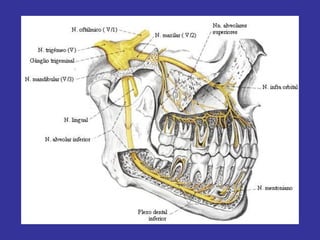

Nervo trigêmeo (V par)

V – NERVO TRIGÊMEO

• Misto

• 3 ramos (n. oftálmico, maxilar,

mandibular)

• Raiz sensitiva => gânglio de Gasser

(trigeminal, semilunar) => cavo

trigeminal - (parte petrosa do temporal)

• Sensibilidade da cabeça=>impulsos

exteroceptivos e proprioceptivos

• Impulsos exteroceptivos (temperatura, dor,

pressão, tato)

 Da pele da face e fronte

 Da conjuntiva ocular

 Mucosa da cavidade bucal, nariz e seios

paranasais

 Dos dentes

 Dos 2/3 anteriores da língua

 Da maior parte da dura máter

• Impulsos proprioceptivos originam-se em:

Músculos mastigadores

Articulação temporo-mandibular

• Raiz motora =>

fibras que acompanham nervo

mandibular,

músculos mastigadores (temporal,

masséter, pterigóideo lateral e medial,

milo-hiódeio, ventre anterior do músculo

digástrico),